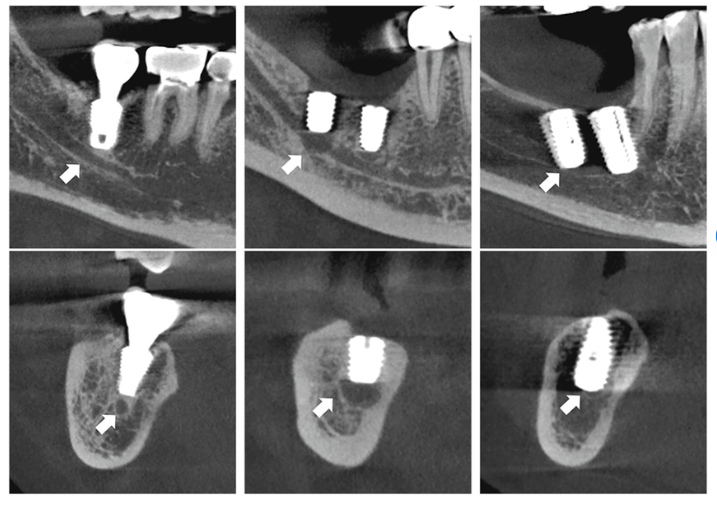

Khi cấy ghép Implant ở hàm dưới, đặc biệt là vùng răng hàm, nếu bác sĩ đánh giá sai vị trí hoặc độ sâu khoan, mũi khoan có thể chạm hoặc xâm lấn vào dây thần kinh răng dưới. Hậu quả có thể gây tê môi, má, cằm hoặc giảm/mất cảm giác vùng mặt, ảnh hưởng lớn đến sinh hoạt hàng ngày của bệnh nhân.

Vị trí đặt trụ cấy ghép có nguy cơ xâm phạm dây thần kinh răng dưới (mũi tên).

Nguyên nhân thường gặp là do thiếu phim chụp CT 3D, không sử dụng máng hướng dẫn phẫu thuật hoặc kinh nghiệm lâm sàng của bác sĩ chưa đủ để xử lý các ca xương hàm phức tạp.

Ở hàm trên, phía trên các răng hàm là xoang hàm – một cấu trúc giải phẫu rất nhạy cảm. Nếu tính toán sai chiều cao xương hoặc đặt trụ không đúng hướng, trụ Implant có thể xuyên thủng sàn xoang hoặc rơi lọt vào xoang hàm, buộc phải can thiệp phẫu thuật để lấy trụ ra.

Đây là biến chứng nghiêm trọng, thường xảy ra khi không đánh giá chính xác thể tích xương còn lại hoặc không áp dụng các kỹ thuật nâng xoang – định vị Implant phù hợp.